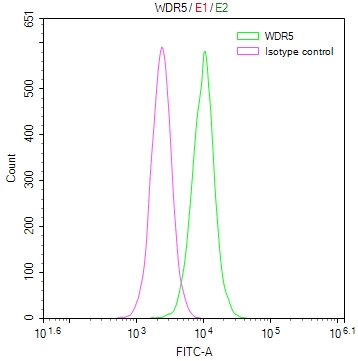

IHC image of CSB-PA896505DSR2HU diluted at 1:50 and staining in paraffin-embedded human Lung cancer performed on a Leica BondTM system. After dewaxing and hydration, antigen retrieval was mediated by high pressure in a citrate buffer (pH 6.0). Section was blocked with 10% normal goat serum 30min at RT. Then primary antibody (1% BSA) was incubated at 4°C overnight. The primary is detected by a Goat anti-rabbit polymer IgG labeled by HRP and visualized using 0.05% DAB. Secondary antibody only control: uses 1% BSA instead of primary antibody